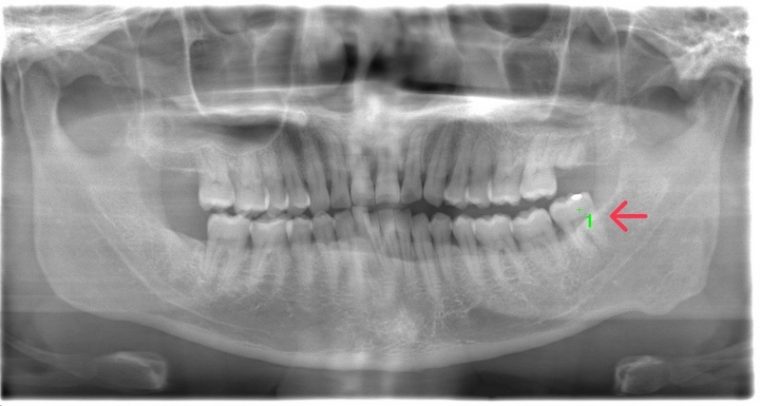

CASE 10

| 年齢・性別 | 39歳・男性 |

| 主訴 | 左上下親知らず抜きたい |

| 抜歯期間 | 30分 |

| 抜歯費用 | 約2,500円(保険内) 別途CT撮影で3,000円 (2022年7月現在) |

| 抜歯内容 | 左上下の親知らず抜歯 |

| 治療方針 |

親知らずは抜いたほうが良い認識はあったものの、痛みや腫れが出ることを知って、勇気が出ないままでいたとのことでした。 そのまま放置していたら虫歯になってしまい、今回ご来院されました。しっかりと麻酔をして緊張をほぐしながら抜歯を始めました。完全萌出のため、時間を要することなくすぐに抜歯することができました。 |